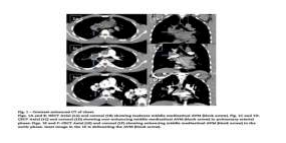

A chest radiograph revealed a mildly bulky right hilum. Non-enhanced computed tomography (CT) of the chest revealed abnormal isodense soft tissue in the middle mediastinum (Figs. 1A and B). CT pulmonary angiogram phase revealed no obvious pulmonary arterial feeders (Figs. 1C and D). Contrast-enhanced CT of the chest in the aortic phase revealed an irregular meshwork of intensely enhancing dilated serpiginous vessels in the middle mediastinum of size 3.5 × 3.0 cm located in the right hilar region, around the right main bronchus (Figs. 1E and F).

A small component of the meshwork was noted in the subcarinal region. These findings were in favor of AVM. The lesion was enhanced in the aortic phase suggesting its supply from the bronchial artery. So, for better delineation of angioanatomy, digital subtraction angiography (DSA) was considered. A finding of achalasia cardia was noted. DSA of the aorta and selective angiograms of the right intercostobrachial trunk gives rise to the first bronchial artery (Fig. 2A), a second bronchial artery from the aorta (Fig. 2C), left bronchial artery and posterior intercostal arteries confirmed the middle mediastinal AVM supplied by 2 right bronchial arteries and draining into the right superior pulmonary vein (Figs. 2A and C).